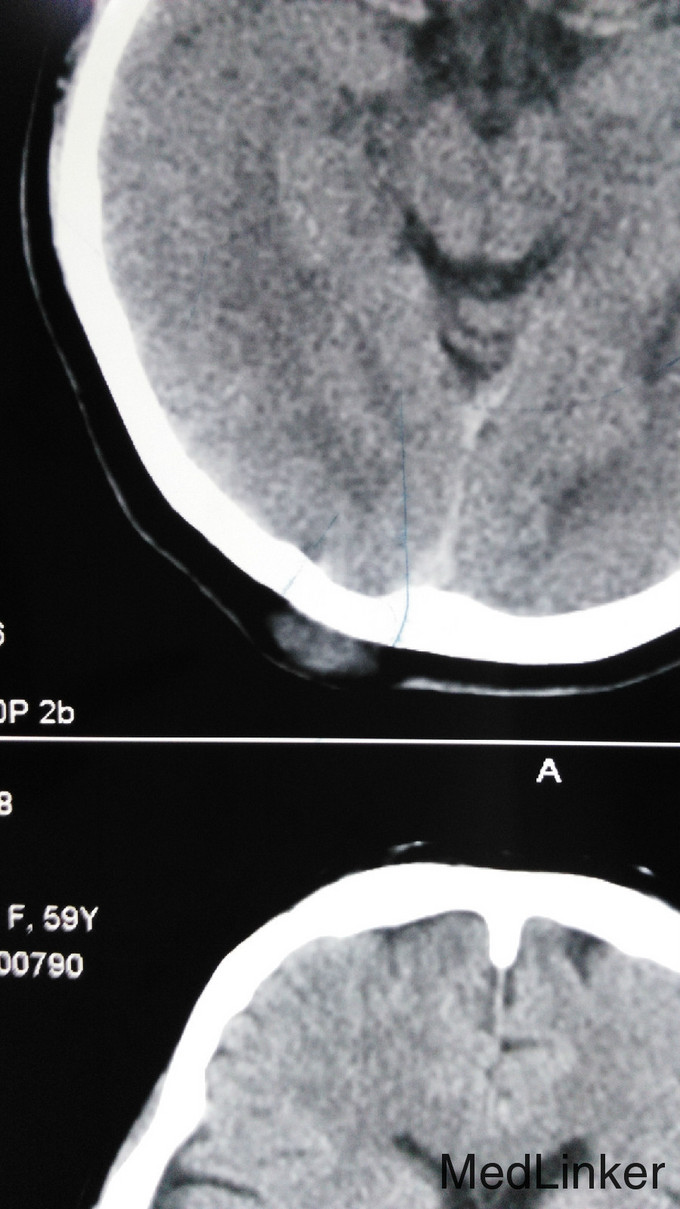

查体:浅表淋巴结未触及,左乳腺未触及包块。 辅助检查:CEA、CA125、CA153正常。上腹部CT正常,妇科彩超未见异常,胸部CT示左肺下叶小结节,直径0.5cm,头CT示头皮下脂肪瘤。